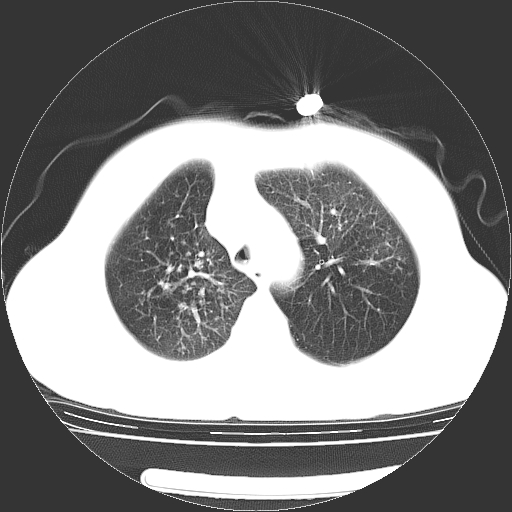

女,70岁,咳嗽、咳痰一个月,低热一周。

1.左上肺结核,部分纤维化。右肺中下叶部分肺不张,内见液化、坏死及点状钙化,右中下叶支气管壁增厚、管腔狭窄,见多个点状钙化,结合临床考虑支气管内膜结核,建议痰检查抗酸杆菌并参考血沉。两肺多个小圆点状高密度灶,境界模糊,多考虑结核肺内播散。但本人年龄较大首先应支气管镜检以除外右肺癌。